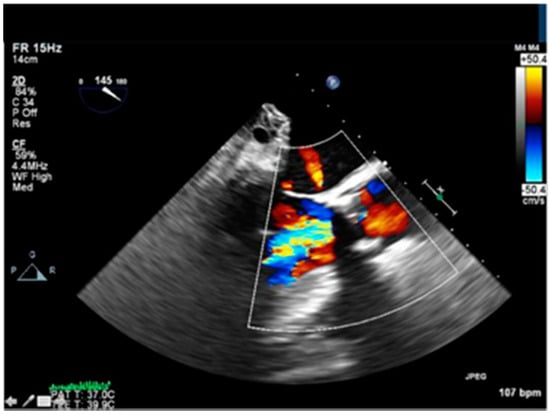

Post valvuloplasty, the patient developed significant acute aortic regurgitation with hemodynamic instability as shown in Figure 3.

Figure 3.

Intraoperative Trans-esophageal echocardiogram showing severe aortic regurgitation.